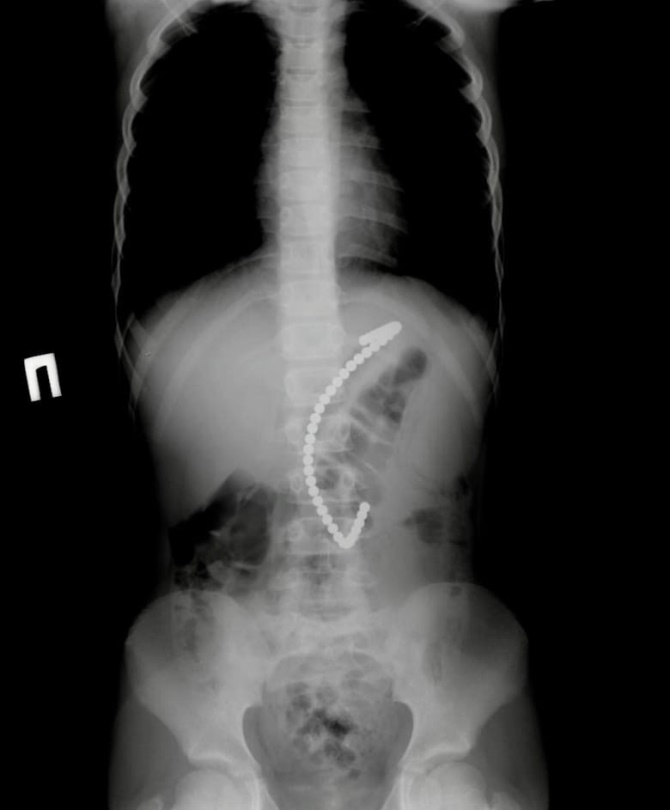

Магнитные шарики на рентгене: Интересные находки

Раздел: Картинки на заметку